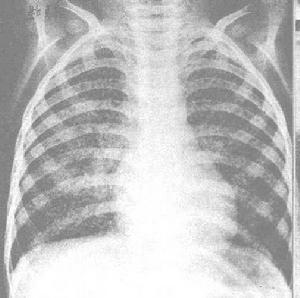

病例選擇所有病例符合以下標準:①經過HRE(Z)S/HRE或DRE(Z)S/DRE方案正規治療6月以上,痰結核分支桿菌陽性或X線胸片病灶仍有進展。②藥物敏感試驗顯示結核菌對HRE等多種藥物耐藥;③年齡18~66歲,平均38歲,無心、肝、腎、耳疾病及矽肺、肺外結核、糖尿病、精神病患者。④未用過卡那黴素B治療。其中治療組42例,男30例,女12例,年齡18~66歲,平均38歲。浸潤型肺結核34例,慢性纖維空洞型肺結核8例;胸片顯示空洞者13例。對照組38例,男30例,女8例;年齡22~63歲,平均40歲。浸潤型肺結核31例,慢性纖維空洞型肺結核7例。胸片顯示空洞者10例。

病灶吸收及空洞改變情況見表2。療程結束時病灶吸收好轉率治療組80.9%,對照組63.1%,兩組間差異有顯著性(P<0.05),空洞閉合率治療組61.5%,對照組30.0%,兩組間差異也有顯著性(P<0.05)。